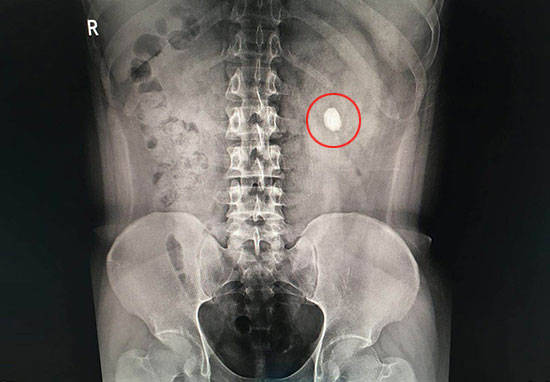

如果发现有尿液发红,需要及时检查泌尿系X光、彩超(首选),化验尿常规及尿沉渣,据此判断是否是尿路结石,彩超可判断结石大小、部位、形态等,没有B超我们选x线,泌尿系平片(KUB)能发现95%以上的结石。如果发现是膀胱结石,需要进行膀胱镜确诊并进行取石。

昨晚上夜班来了一个急腹症的男病人,36岁,说是近半个月来出现尿液发红,时有时无,特别是活动后最容易出现左侧肾区疼痛,当时也没有重视进一步检查,这不突然出现左侧肾区剧烈疼痛,像撕裂一样,还向会阴部放射,疼得浑身出汗,忍受不了才来医院看看,经检查是:双侧肾盂结石,左侧输尿管结石梗阻,左侧肾积水,当时邀请碎石科给予急诊碎石治疗后,疼痛缓解了,复查泌尿系彩超提示:左侧输尿管结石梗阻解除。相信大家对结石都有所耳闻,今天就来说说导致尿液发红的泌尿系结石,您可要注意了。